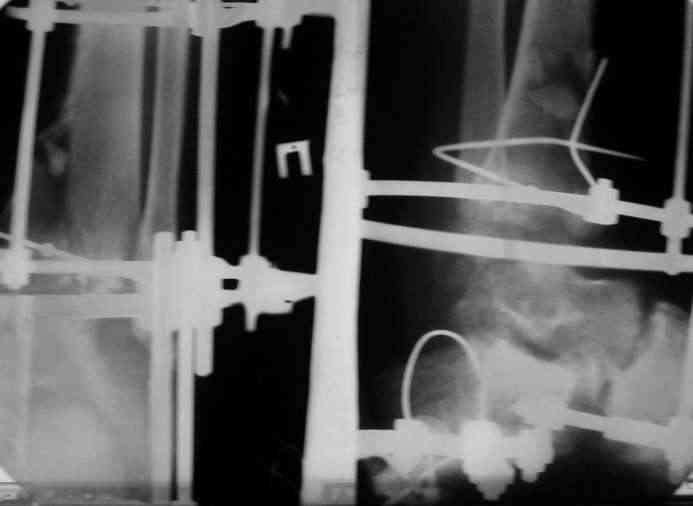

Вчера (прошло около 8 месяцев)больной обратился ко мне в очередной раз с жалобами на боли умеренно-жгучего характера в области выстояния концов болта-стяжки. На момент осмотра:укорочение левой нижней конечности на 1,5 см; гипотрофия медиальной группы мышц голени и четырехглавой мышцы бедра; передвигается без дополнительной опоры в ортопедической обуви на растояние до 5 км; работает приемщиком цветных металлов (приходится перетаскивать грузы). Нарентгенограмме, насколько это можно видеть, костного блока сформировать не удалось, но движений в голеностопном суставе нет - ни активных, ни пассивных. Послеоперационные рубцы б/о; свищей и нагноения не было. Активно больногонаблюдать не приходилось, т.к. проживает в другом городе.

Стоит ли необходимость удаления болта-стяжки из-за болевого синдрома?

ЗЫ: Прошу прощения за очень низкое качество представленных ренгенограмм. Буду очень признателен за комментарии.